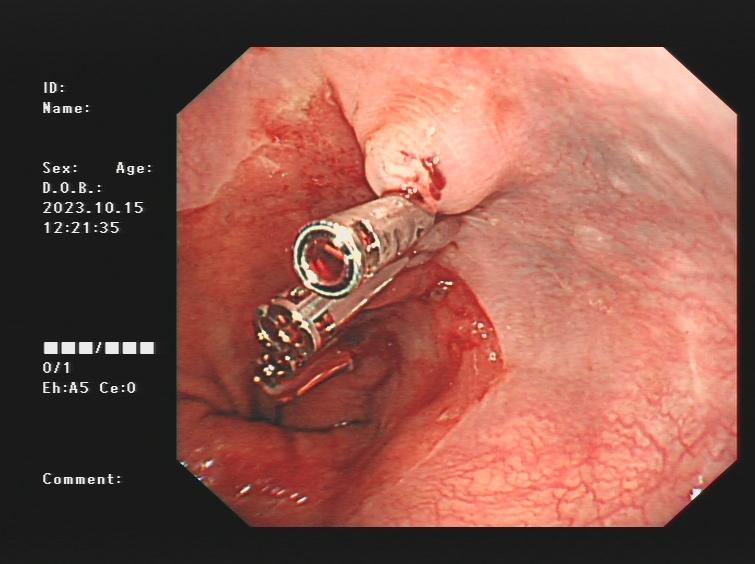

1.上消化道出血常见原因:消化性溃疡(胃溃疡、十二指肠溃疡)、食管炎、急性糜烂出血性胃炎、上消化道肿瘤(食管癌、胃癌)、剧烈呕吐造成的食管贲门黏膜撕裂伤、肝硬化引起的食管胃底静脉曲张。以下是一些常见的上消化道出血内镜图片:

肝硬化引起的食管及胃底重度静脉曲张镜下止血